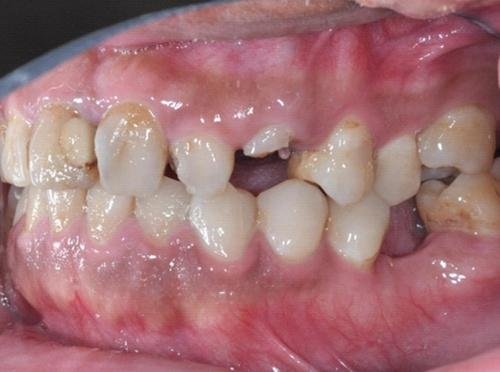

一位32歲男子近年來飽受牙痛問題,但卻一直沒有接受治療,最近到大醫院就診,透過環口X光及口腔檢查之後,發現有多項牙齒問題,包括齒列擁擠、缺牙、牙傾倒、對咬牙過度萌出、深部齲齒、牙周炎、齒髓炎等,已經影響患者咀嚼功能及美觀。

收治這位男子的台南市立醫院牙科部張閔傑醫師指出,由於患者的牙齒問題多且複雜,牙科團隊第一階段先進行齲齒填補、牙周病控制、以及裂齒拔除;第二階段透過矯正,將過深齲齒拉出、扶正傾倒的後牙、騰出足夠空間,製作臨時牙冠,進行永久義齒的製作,讓患者慢慢恢復牙齒健康美觀。

張閔傑醫師表示,一旦缺牙過久,會使周圍臨近的牙齒朝向缺牙區域傾倒,將導致製作假牙時,需修磨較多的牙齒結構,也可能會傷及牙髓組織;此外,對咬牙朝向缺牙區域移動,將導致咬合干擾,遇到牙齦下齲齒過深無法製作假牙、牙齒外傷斷裂等,可透過矯正將牙齒拉出,伴隨牙周手術,才得以進行義齒製作。

由於患者同時有牙周病的困擾,牙周病常伴隨牙齒擁擠導致清潔不易,加速牙周惡化,因此,接受牙周照護的同時,搭配矯正治療將齒列排列整齊,可使患者更易維持口腔衛生,並維持牙周健康。矯正醫師曾上純指出,近年來植牙盛行,透過矯正治療一同進行,可幫助無法修復的牙齒進行移動,得到較多骨頭,改善後續植牙治療所需條件,最後再把這些無法修復的牙齒予以拔除,才可達成植牙最佳效果。